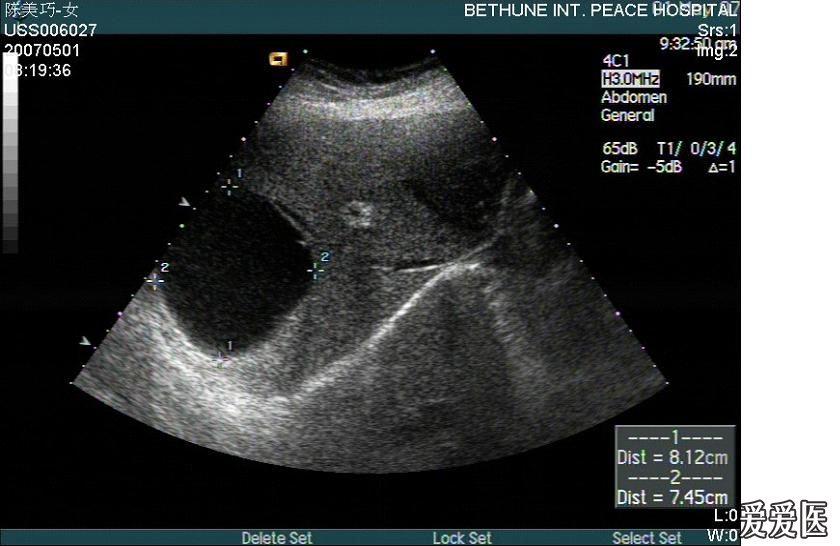

乳腺囊肿病情一般主要是高发于哺乳期间,在青春期,以及绝经期可谓是罕见。一般情况下,乳腺囊肿的症状表现都是比较明显的,同大多数乳腺疾病相同的是,都具有肿块,但主要是以圆形或者是椭圆形为主,剧烈疼痛伴触疼常为乳腺的炎症性表现。局部疼痛,多见于乳腺的单纯性增生和囊性增生。乳癌病人,为轻微疼痛,疼痛性质为钝痛、隐痛,局限于病变处针刺样疼痛,有时呈间断性。那乳腺囊肿如何治疗?小编马上来告诉你。

如果大家都不重视健康,严重的疾病就容易出现在我们的身上。乳腺囊肿疾病容易出现在青年女性的身体上,这个时候女性就应该尽快接受治疗,采用有效的手术治疗方法,能够彻底的切除患者的病房,物理治疗方法,能够有效地去除患者身体上的疼痛,那么乳腺囊肿的最佳治疗方法有哪些?